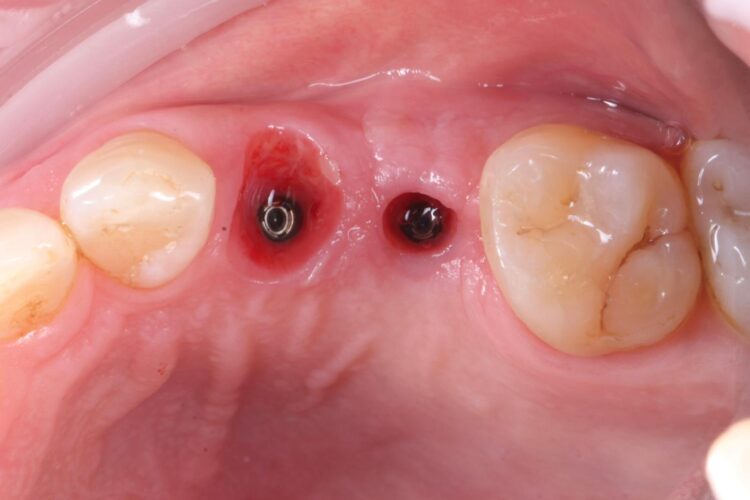

Upon presentation, the initial assessment suggested that an immediate implant may be viable for the UL4 site, alongside simultaneous implant placement in the already healed UL5 site.

A comprehensive clinical assessment was conducted. The patient was generally fit and healthy, was taking no medication, had no allergies and maintained fair oral hygiene. The UL5 site, which had been edentulous for approximately seven years, presented with a substantial depression. This made immediate and simultaneous implant placement even more appropriate for the UL4/5, utilising the bone peaks around the UL4 to create a more favourable UL5 implant position and simultaneous augmentation. Other findings of note were signs of tooth wear on the UL3 and UL6, although these were periodontally sound and completely stable.

The UL4 root was extracted as atraumatically as possible. The roots were thin and spindly, and needed to be split to be removed safely. They were sectioned in a mesial-distal direction to leave the buccal and palatal roots separate, reducing the risk of fracture and preserving the interdental and surrounding bone.

The surgical guide was then placed in the mouth and the manufacturer’s specific drilling sequence followed, increasing the osteotomy in size incrementally.